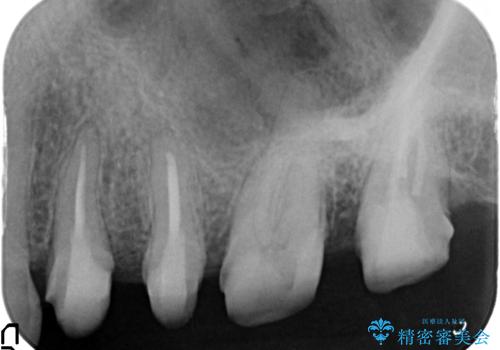

放置した虫歯 根管治療 フルジルコニアクラウン

- 虫歯治療を途中で中断し放置した歯の治療再開を希望され来院されました。

樹脂やクラウン・銀歯の老朽化がみられるため、丁寧に除去を行い根管治療を行ったのち、歯軋り・厚みの少なさを鑑みフルジルコニアクラウンによる補綴を計画します。